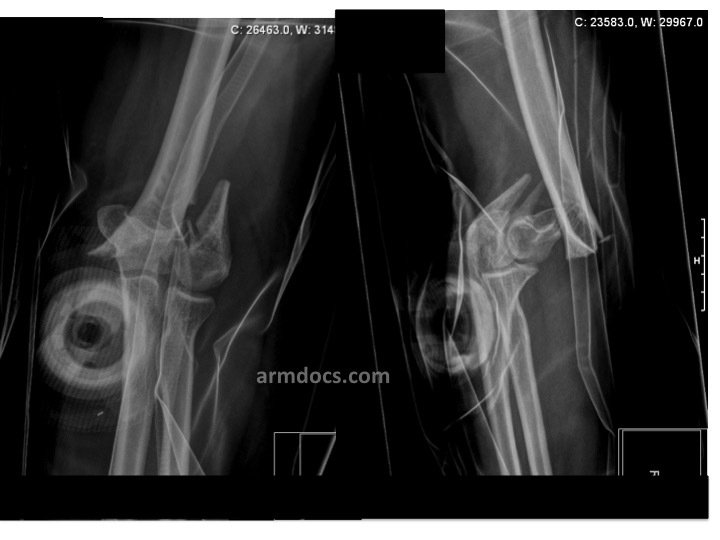

Fractures of the distal humerus may be suspected from the mechanism of injury resulting in pain, deformity and bruising over the outer aspect of the elbow. The diagnosis is confirmed on X-rays of the elbow. In most instances a CT scan will be arranged to study the fracture in greater detail and help plan surgical treatment.